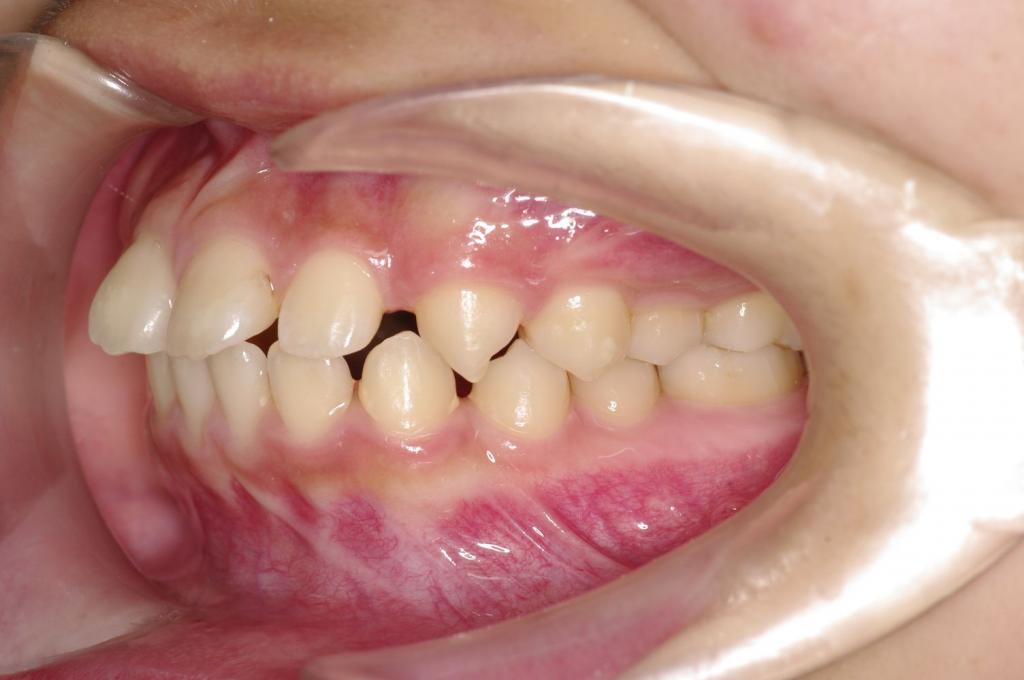

前歯、出っ歯・開咬の矯正治療

(治療期間、治療前後写真、治療方法、費用)WORKS